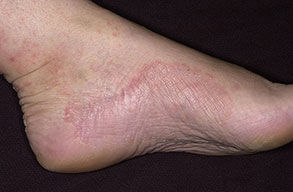

Chronic Intertriginous Type (Interdigital Type).

The most common presentation of tinea pedis, the chronic intertriginous

type, begins as scaling, erosion, and erythema of the interdigital and subdigital skin of the feet, particularly between the lateral three toes. Under appropriate conditions, the infection will spread to the adjacent sole or instep, rarely involving the dorsum. Occlusion and bacterial co-infection soon produce the interdigital maceration, pruritus, and malodor of dermatophytosis complex